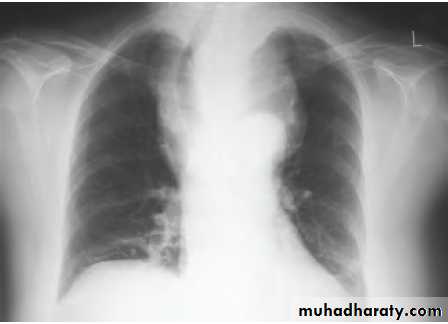

Retrosternal goitre

Arise from the slow growth of a multinodular gland down in to the mediastinum.As the gland enlarges within the thoracic inlet, pressure may lead to dysphagia, tracheal compression and eventually airway

symptoms.

Patient should be considered for surgery if there is significant airway compression